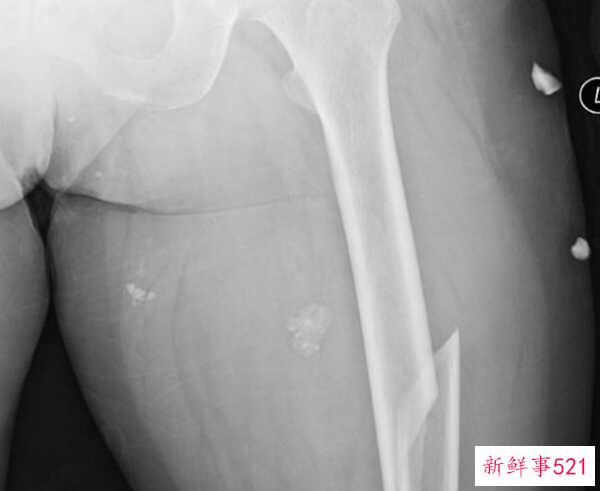

7.股骨骨折人最痛苦的是什么?揭秘人世间最痛苦的10件事

股骨或股骨是人体最大的骨头,股骨骨折是人可能经历的最痛苦的骨折。即使在痊愈的过程中,也是艰巨的,通常需要四到五个月,并且可能在恢复多年后继续受到一些因素的影响。